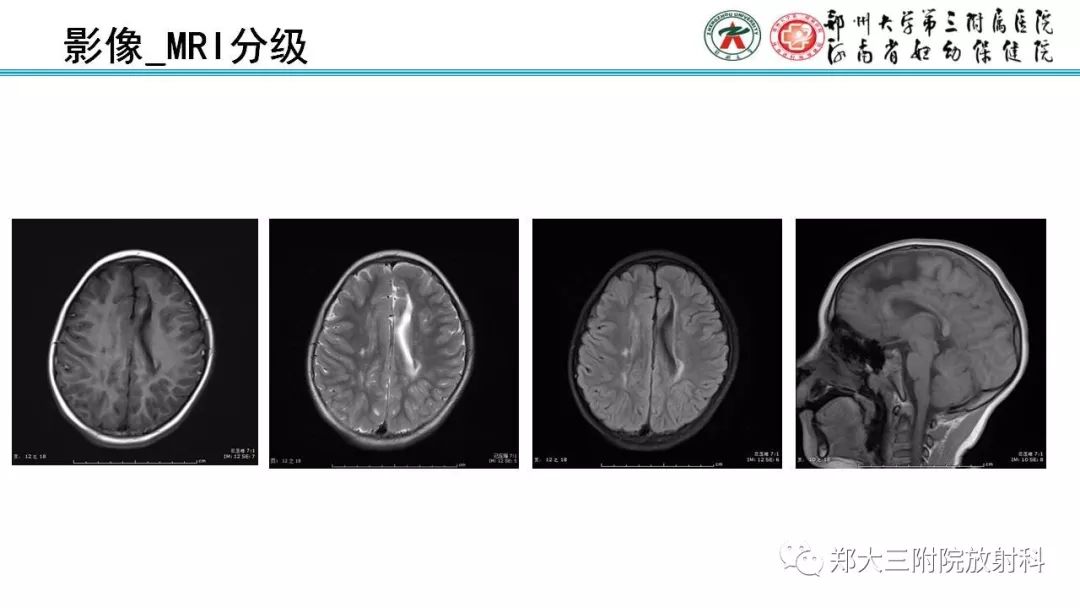

PVL脑室周围白质软化症的影像表现

【PPT】PVL脑室周围白质软化症的影像表现